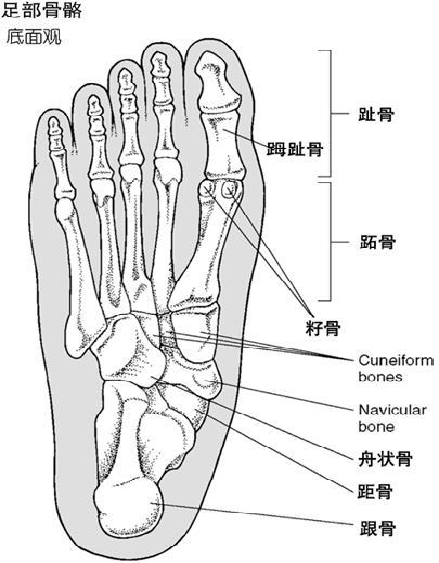

第1跖趾关节周围软组织解剖示意图

拇外翻的解剖特点

第1跖趾关节由两个关节构成:跖骨头关节面延伸于跖骨头的跖侧,并被一嵴分为两个斜形关节面分别与胫、腓侧籽骨成关节;第1跖骨头远端呈椭圆形,与近节趾骨基底的凹形关节面形成关节。

第一跖趾关节两侧有扇形的侧副韧带、止于籽骨的悬韧带,跖侧有厚韧的足底韧带(又称为跖板)

拇趾籽骨是组成第1跖趾关节的重要结构,起着保护屈拇长肌腱和跖骨头的作用,同时类似一个滑车增加了屈拇长、短肌腱的力量。

拇趾跖趾关节周围有6条肌腱通过或附着足背侧

• 拇长伸肌腱通过关节背侧止于远节趾骨基底背侧。

• 拇短伸肌腱止于近节趾骨基底背侧。

• 拇展肌腱止于近节趾骨基底内侧。

足底侧

• 拇长屈肌腱通过内、腓侧籽骨间沟,向远侧止于远节趾骨基底.

• 拇短屈肌腱在跖趾关节跖侧分为内、外侧腱两部分,分别经籽骨止于近节趾骨基底内、外侧跖面

第1跖趾关节可主动背伸50°~ 60°,被动背仲最大可达90°;主动跖屈30°~ 40°,被动跖屈45°~50°